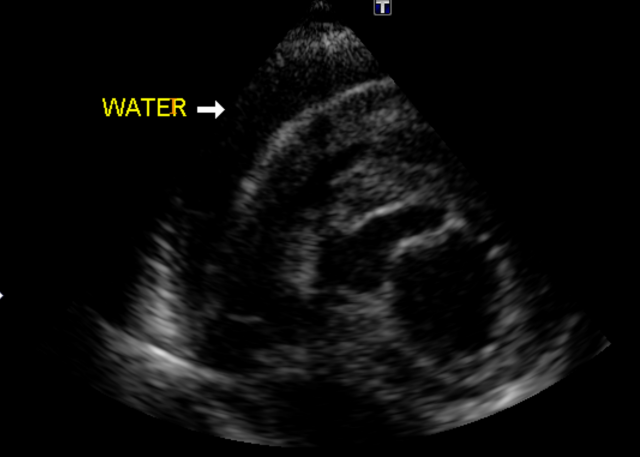

心臓エコー検査にて、心嚢水、右心房の虚脱を確認。また腫瘍や心臓病の確認もできます。